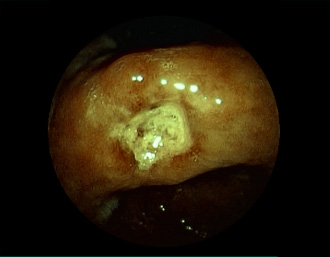

胃カメラ症例

当院で発見された症例の一部をご紹介致します。

胃潰瘍(37才、男性)

健診:胃レントゲン検査で、胃角部ニッシェを指摘され当院受診。

胃角部小弯に、深くて大きな、大きさ約10mmの胃潰瘍(stage 1)があり、潰瘍底は一部白苔はみ出しを認める。エソメプラゾールマグネシウム水和物投薬で治療開始しました。

通常画像

FICE画像